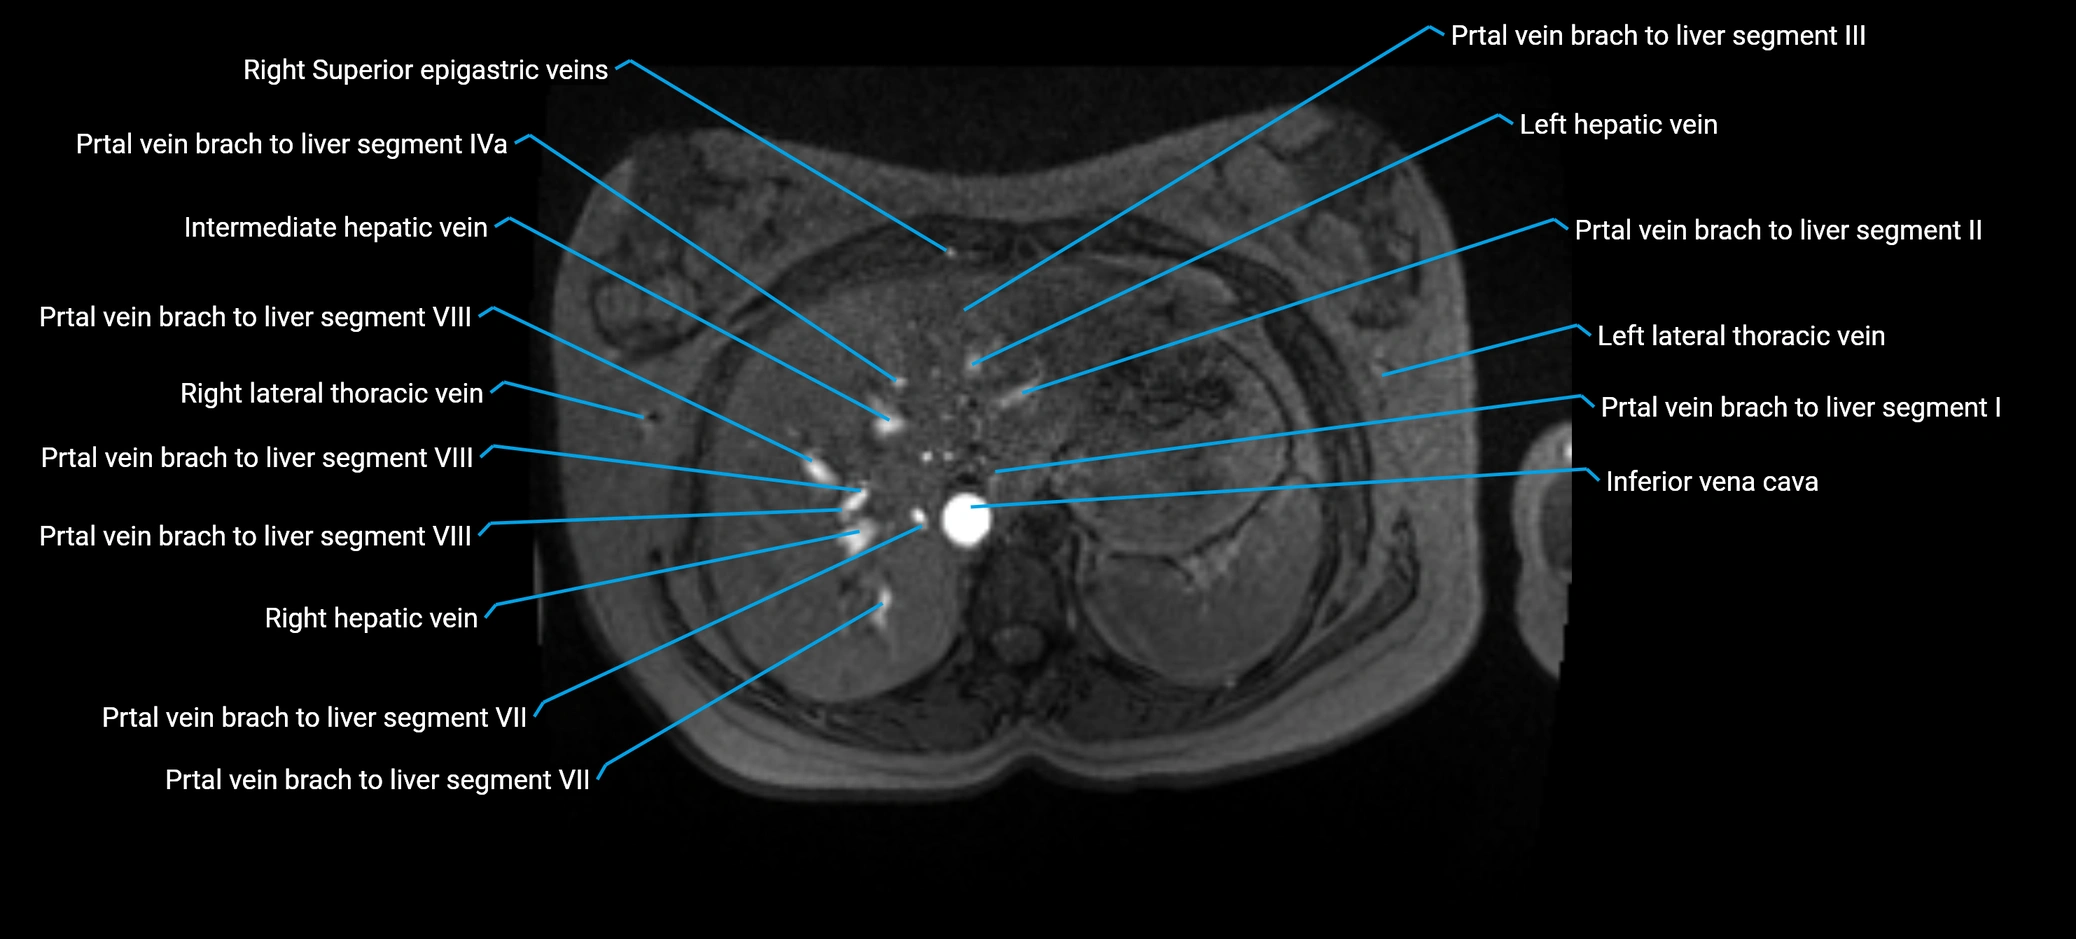

MRV TOF (Time-of-Flight MR Venography):

• Appears as a bright, high-signal vascular channel representing flowing blood

• Clearly shows branching pattern of right portal vein into anterior and posterior branches

• Best in coronal or axial reconstructions for segmental mapping

• No need for contrast, relies on flow-related enhancement

MRI image

image